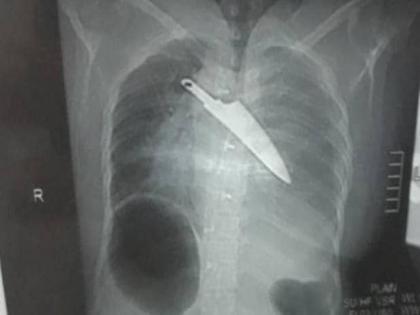

एका महिलेच्या शरीरातून डॉक्टरांनी घटनेच्या तब्बल 30 तासांनंतर एक चाकू काढला. 3 तासांच्या सर्जनीनंतर डॉक्टरांनी हा चाकू बाहेर काढला. ही घटना तामिळनाडूच्या कृष्णागिरी जिल्ह्यातील होसुर येथे घडली. महिलेचं नाव मल्लिका असून तिचं वय 40 सांगण्यात आलं आहे.

मल्लिकावर 25 मे रोजी हल्लेखोरांनी हल्ला केला होता. तिच्या शरीरात चाकू मारण्यात आला होता. पण तिला याची अजिबात कल्पना नव्हती की, संपूर्ण रात्र चाकू तिच्या छातीत राहिल्यावर ती वाचेल की नाही. घटनेच्या 24 तासांनंतर कोयम्बटूर मेडिकल कॉलेज हॉस्पिटलच्या डॉक्टरांना 3 तासांच्या सर्जरीनंतर महिलेच्या शरीरातून चाकू काढण्यात यश मिळालं.

हा चाकू 6 इंचापेक्षा अधिक लांबीचा होता. महिलेच्या फुप्फुसाच्या छोट्या भागात चाकूमुळे छिद्र पडलंय. सुदैवाने महिलेच्या हृदयाला काहीही इजा झाली नाही. डॉ. श्रीनिवासन आणि एनेस्थिसियोलॉजचे प्रमुख डॉ. जयशंकर नारायणन यांच्या नेतृत्वात ही सर्जरी केली गेली.